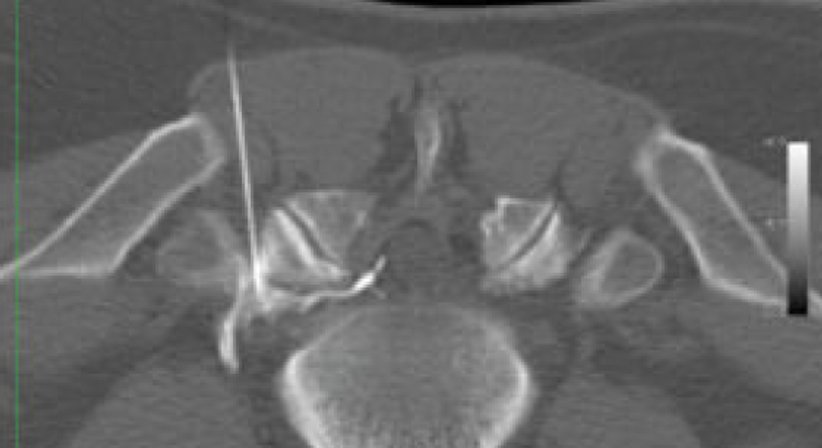

​Ziel der Infiltration

ist eine lokale abschwellende und schmerzlindernde Wirkung direkt am Ort des Geschehens. Dies bewirkt meistens eine sofortige Besserung der Beschwerden. Das Verfahren kann zur effizienteren Wirkung mehrfach wiederholt werden.

• Facettengelenksinfiltrationen der HWS, BWS und LWS

• Wurzelblockaden

• Infiltration bei Schmerzen im Iliosakralgelenk (ISG)

• Infiltration bei Karpaltunnelsyndrom und anderer peripherer Nerven

• Epidurale Infiltration (single shot peridural anästhesie)